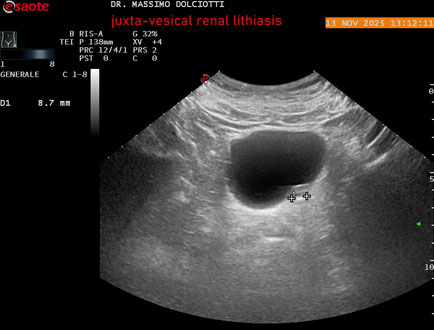

Data inserimento: 14/11/2025

Ecografia del: 13/11/2025

Strumento: Esaote MyLab Eight

Sonda: Convex Multifrequenza 1-8 MHz

Età Paziente: M 59 anni

Motivazione dell'esame: dolori al basso addome ed al fianco sinistro, comparsi la notte precedente.

Commento all'esame: le immagini ed il video documentano al rene sinistro, idronefrosi di 1°-2° grado, con presenza di immagine iperecogena, con cono d'ombra posteriore, allo sbocco dell'uretere sinistro, in sede iuxta-vescicale, delle dimensioni di 6,2 mm, con segno del Twinkling Artifact (o segno di Arlecchino), da ricondurre a litiasi.

Conclusioni: litiasi renale sinistra iuxta-vescicale (left juxta-vesical renal lithiasis).